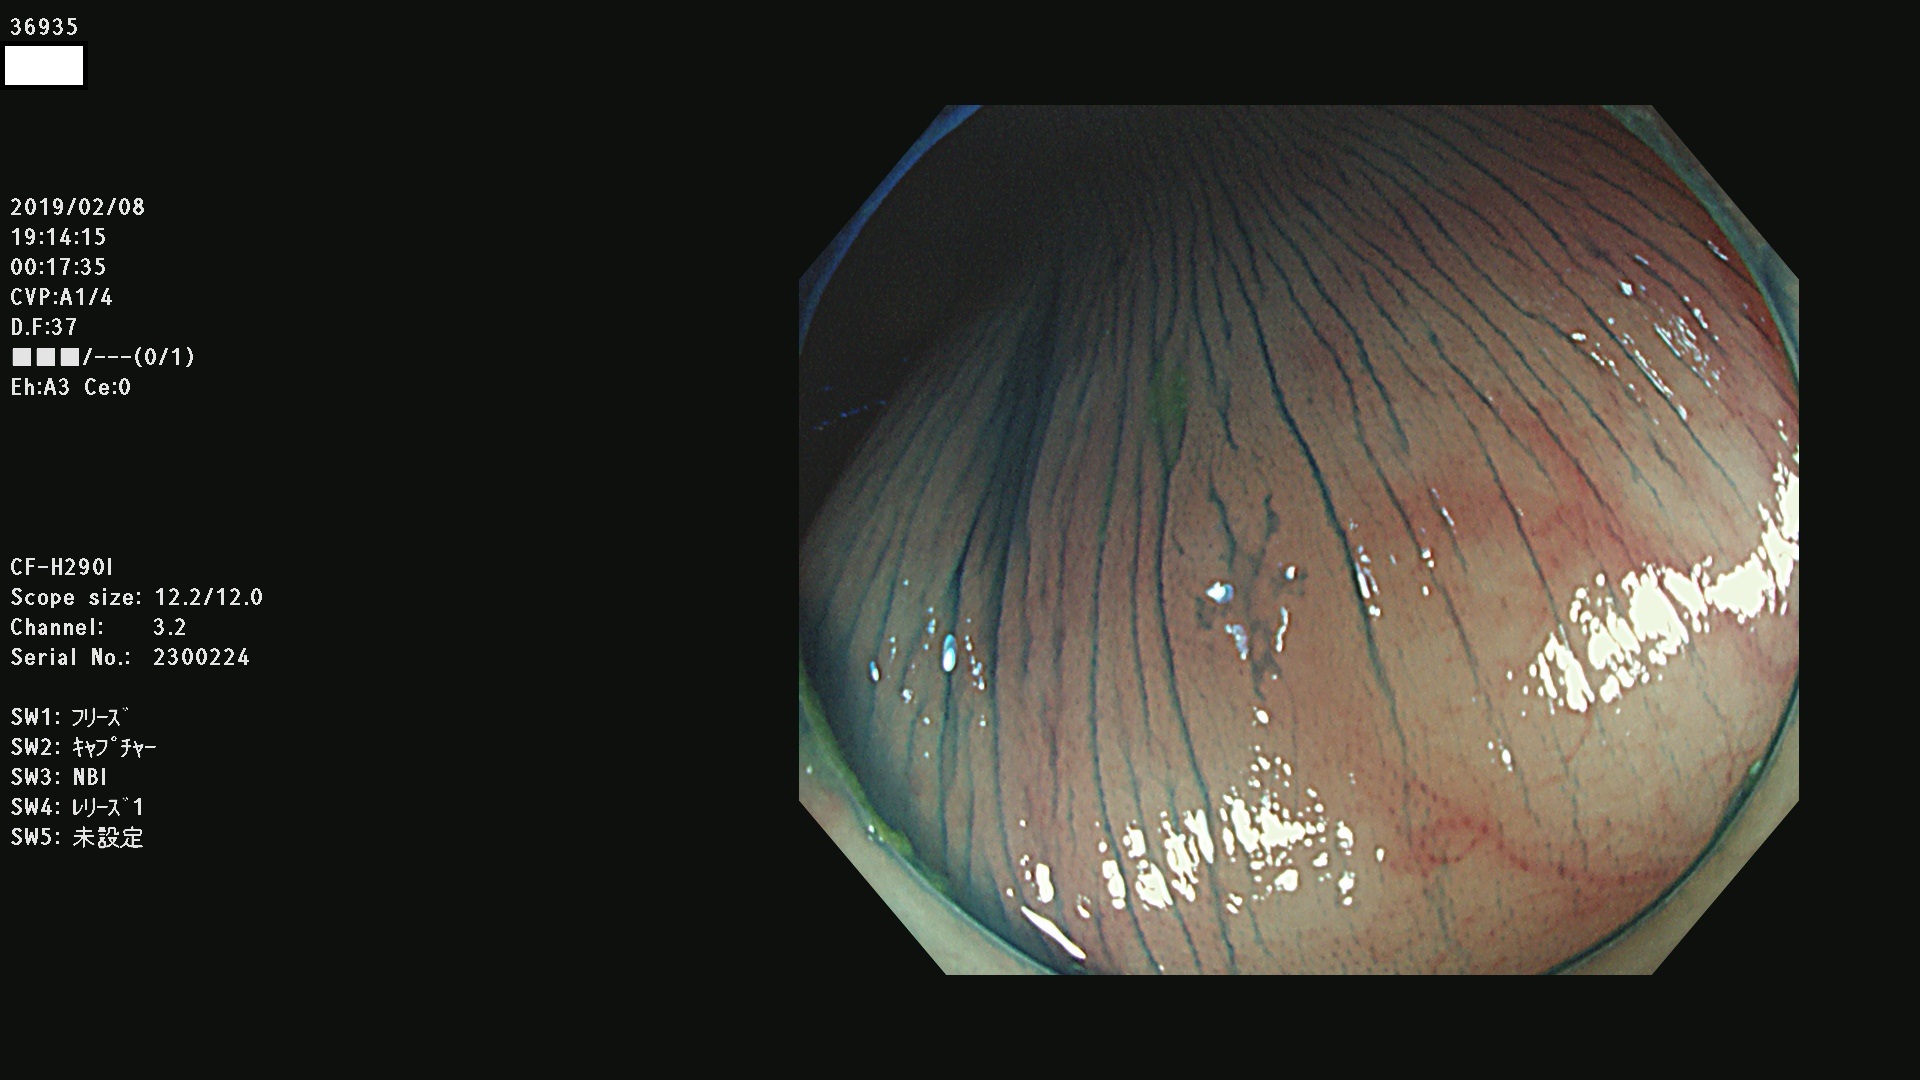

腺腫発見率 67 % (カルテ番号 36900〜36999の100名の方の検査結果で集計)大腸癌検診最新情報

以下のカルテ番号の方に腺腫(Adenoma,Group3〜5)が見つかりました(集計法)

36900 36901 36903 36904 36905 36908 36909 36910 36911 36913 36914 36915 36916 36917 36918 36919 36920 36923 36924 36925 36927 36928 36930 36931(SSAPのみ) 36933 36935 36936 36937 36941 36943 36944 36945 36946 36949 36951 36953 36954 36955 36957 36963 36965 36966 36967 36968 36969 36970 36974 36975 36976 36977 36978 36979 36980 36981 36983 36984 36986 36987 36988 36989 36990 36991 36993 36994 36996 36998 36999

発見困難で危険性の高い平坦型病変(上記100名より抽出) ![]()